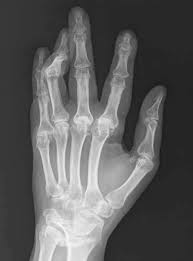

처음에는 관절이 뻣뻣해지고, 손가락, 발가락, 손목, 발목 등 온 몸의 주요관절이 붓고 통증도 동반된다고 한다.

적절한 시기에 치료를 받지 못하면 관절이 변형되고, 변형된 관절은 회복이 불가능하기 때문에 조기 진단과 치료가 매우 중요하다고 한다.